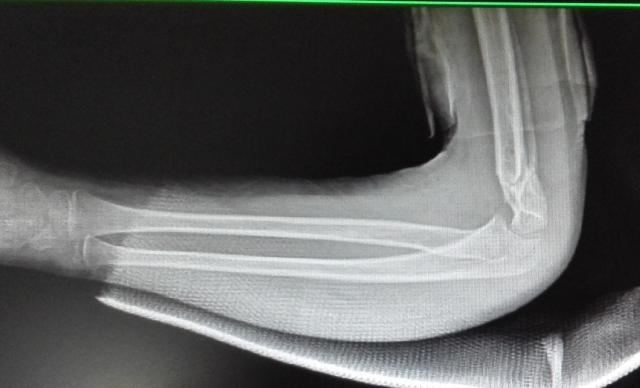

典型病例:中醫(yī)手法整復,夾板固定治療肱骨髁上骨折